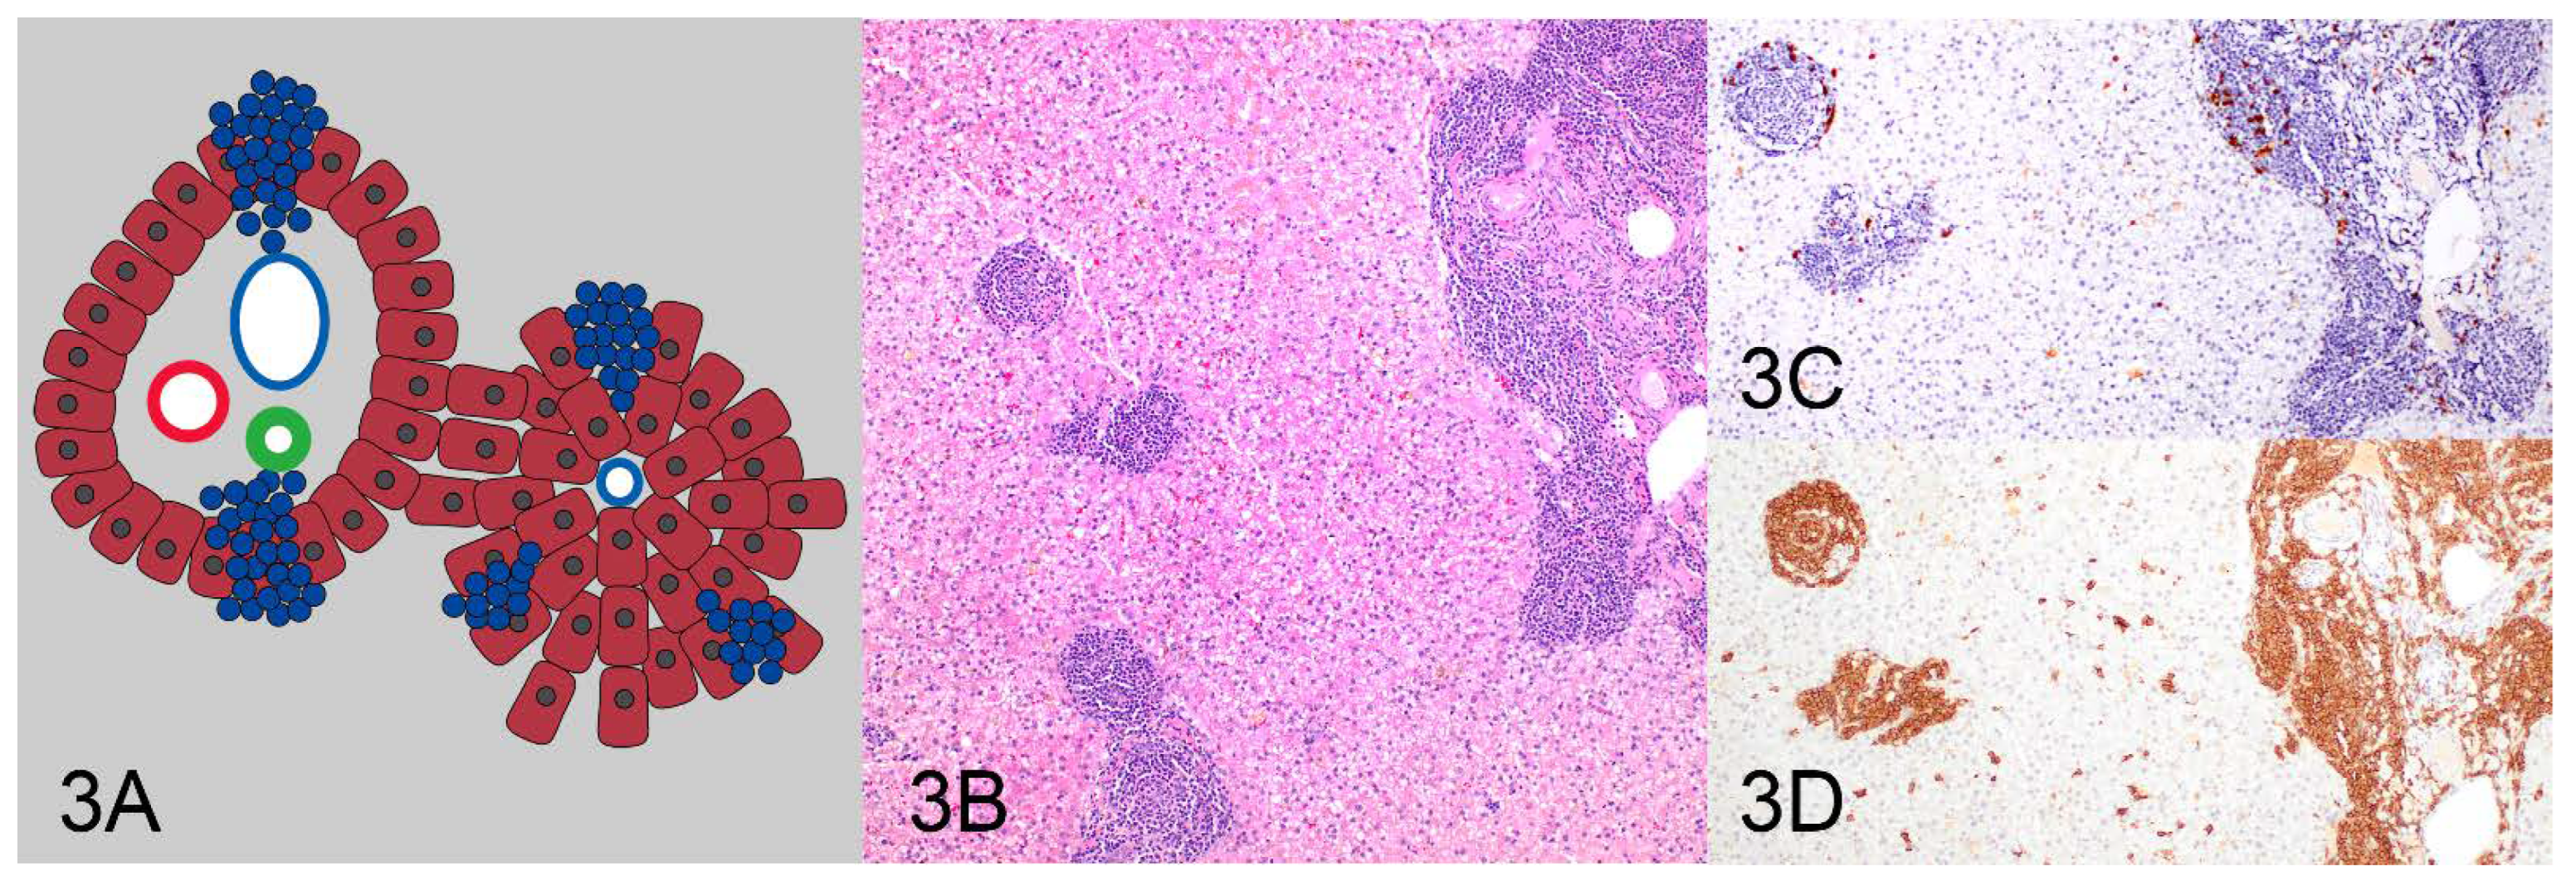

| Pattern 3: Nodular | 0 (0%) | 2 (100%) | 2 (100%) |